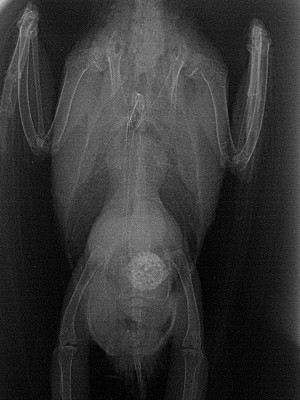

Röntgen

Röntgen ist eine diagnostische Methode, die es ermöglicht, Bilder vom Körperinneren eines Wellensittichs zu machen, um mögliche Verletzungen, Knochenbrüche, Tumore und Veränderungen im Bereich der Brust- und Bauchorgane zu erkennen. Röntgenaufnahmen können auch bei der Diagnose von Atemproblemen helfen.